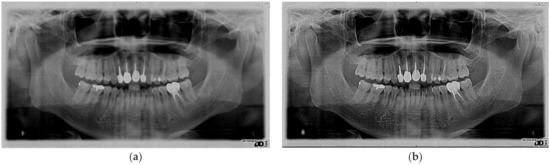

3. Results